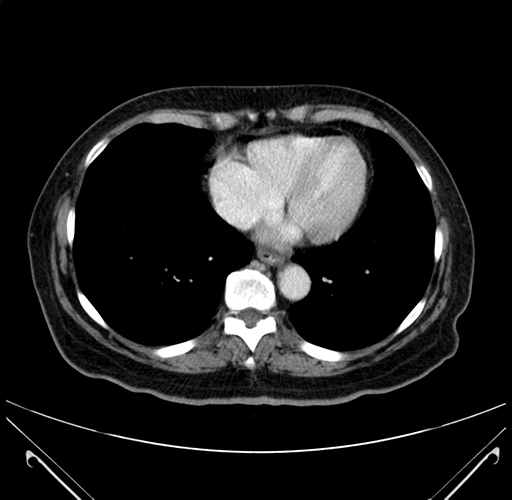

Pre-Chemo: Axial Venous